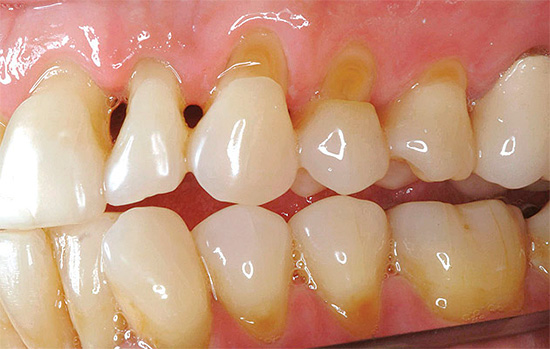

Abaixo estão algumas fotos com exemplos de cárie cervical:

Abaixo está uma foto de cárie cervical no estágio local:

Nas cáries superficiais, a dor geralmente ocorre por irritantes químicos (salgados, doces) e pela temperatura (frio). Externamente, nesta fase, a doença se assemelha à cárie no local da mancha, mas ao sondar um dentista com um instrumento afiado especial (sonda), uma zona de rugosidade é detectada no centro do local vasto.